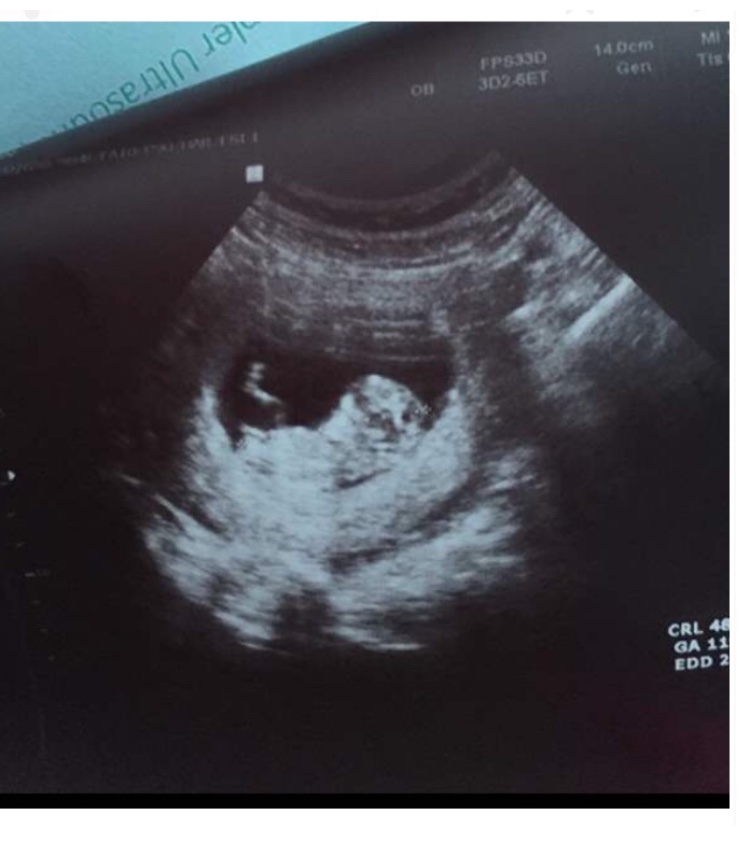

غربالگری اول گفت بچه دختره کسی بوده که اشتباه گفته باشن بهش؟

نه نگف میخای عکسشو بفرستم

عکس نمیاد 😑ولی تو تایپیکام هست منم یکم بهتر شدم نسبت به اوایل کارامم میتونم بکنم